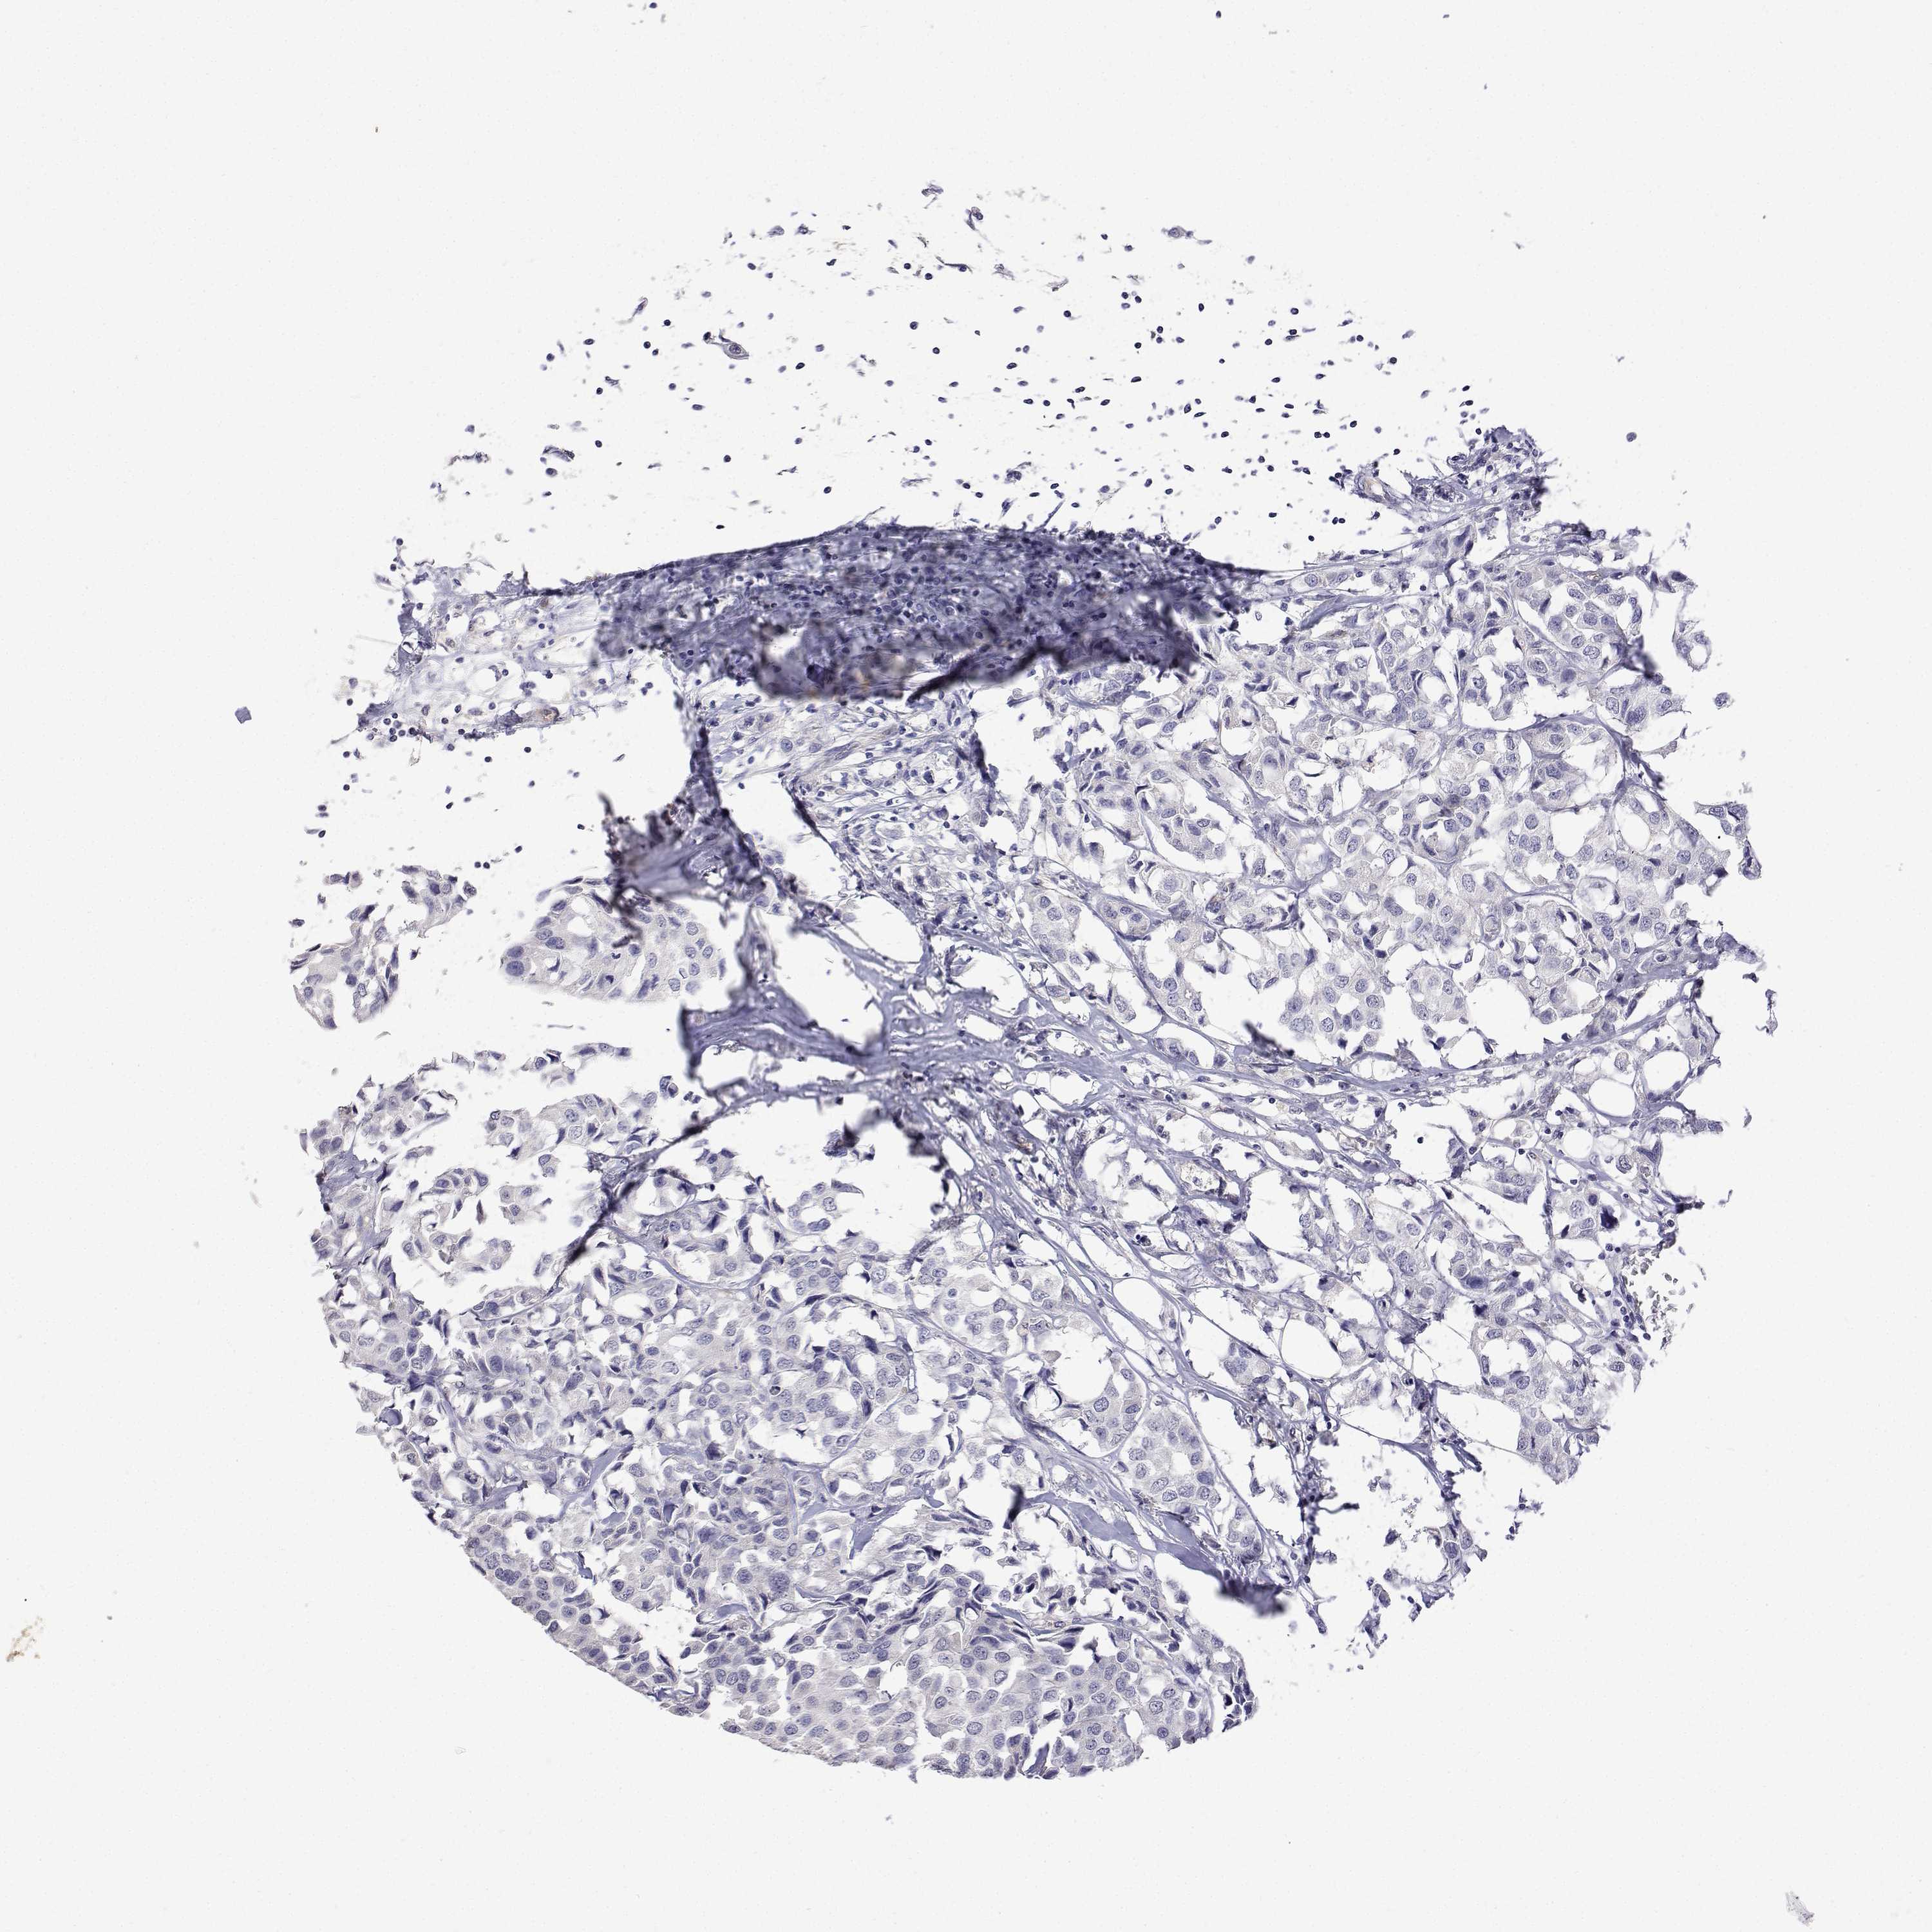

CANCER BREAST CANCER Show tissue menu

BRCA TCGA BRCA VALIDATION PROTEIN EXPRESSION

ANTIBODIES

AND

VALIDATION